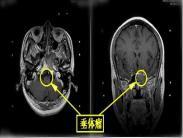

• 垂體腺瘤

628健康網(wǎng)為您分享有關(guān)垂體腺瘤的癥狀,垂體腺瘤的治療方法,垂體腺瘤的預(yù)防知識(shí),垂體腺瘤的癥狀圖片,垂體腺瘤吃什么藥,垂...